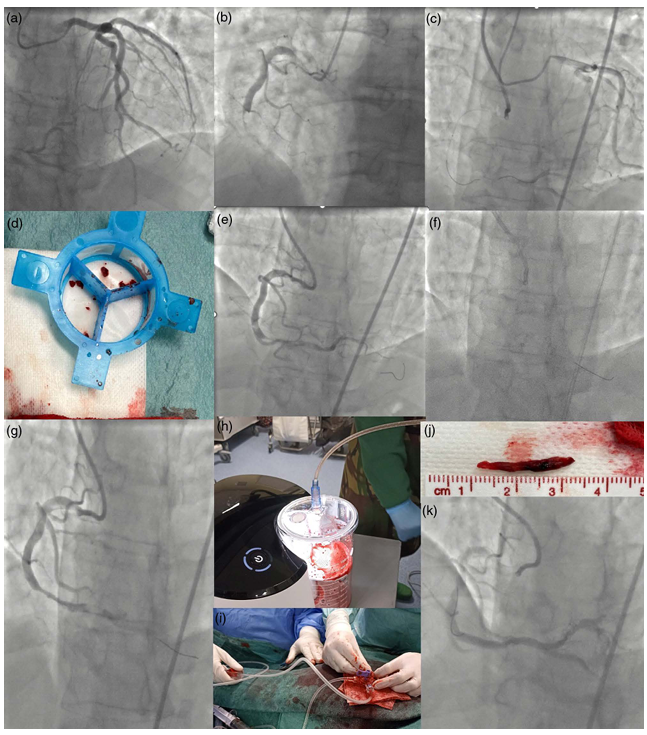

Overcoming thrombus challenges using Penumbra aspiration system connected to Guideliner 7F, in the hands of Tiago Mendonça and Luís Almeida Morais at Hospital Santa Marta Cardiology Find out more about our latest published clinical case at journals.lww.com/coronary-arter…

Overcoming thrombus challenges using Penumbra aspiration system connected to Guideliner 7F, in the hands of <a href="/tjcmendonca/">Tiago Mendonça</a> and <a href="/LusAlmeidaMora1/">Luís Almeida Morais</a> at <a href="/HSMarta_Cardio/">Hospital Santa Marta Cardiology</a>

Find out more about our latest published clinical case at journals.lww.com/coronary-arter…